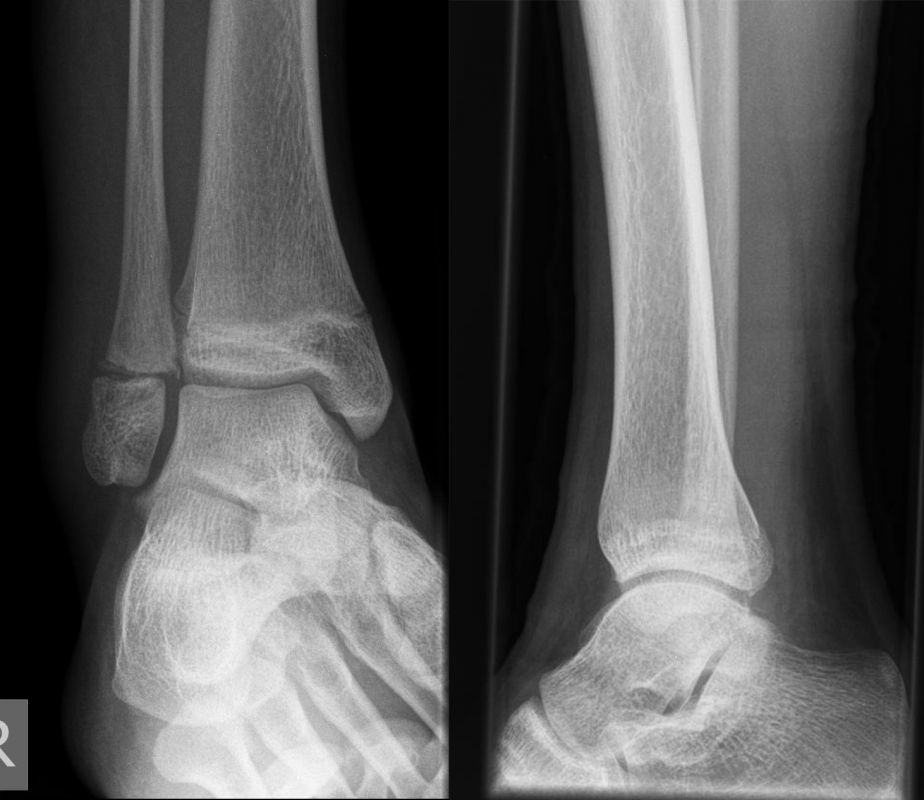

Die Standard Röntgendiagnostik des Sprunggelenks umfasst Bilder in anteriorposterioren (a.p.) und im seitlichen Strahlengang 6. Für die exakte Abbildung des Innenknöchels müssen beide Malleolen parallel zur Röntgenplatte zu liegen kommen. Je nach Torsion der Tibia macht dies eine Innenrotation des Fußes zwischen 10° und 30° erforderlich (Abb. 3).

Manchmal sind mediale Malleolarfrakturen nur in einer der Aufnahmen in ihrem Ausmaß erkennbar. Keine Rolle spielt die gehaltene Aufnahme beim Kind, insbesondere bei der akuten Verletzung. In seltenen Fällen hat dieses Verfahren bei Verdacht auf eine chronische Instabilität eine Berechtigung.

Fugengelenkfrakturen treten typischerweise vor dem 10. Lebensjahr auf, in einer Phase, in welcher die Wachstumsfugen noch weit offen sind. Dieser Frakturtyp betrifft fast ausschließlich den medialen Malleolus. Laterale Frakturen sind extrem selten, teilweise kommt es zu lateralen Bandverletzungen oder Fugenschaftfrakturen der distalen Fibula. Die Frakturlinie verläuft in einer Verlängerungslinie von der medialen Taluskante nach proximal. Häufig stellen sich Verletzungen des Innenknöchels im Röntgenbild schlechter dar, insbesondere wenn die Aufnahmen verdreht sind oder die Ebene der Fraktur bei geringer Dislokation verkippt zur Röntgenebene liegt. Besteht klinisch der geringste Hinweis auf eine Verletzung des Innenknöchels, muss aufgrund der Tragweite der Verletzung durch entsprechende Aufnahmen gegebenenfalls auch Schnittbildverfahren die Verletzung sicher diagnostiziert oder ausgeschlossen werden (Abb. 15).